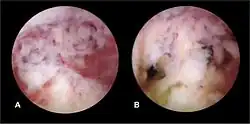

Hysteroscopic view of intrauterine adhesions

The history of a pregnancy event followed by a D&C leading to secondary amenorrhea or hypomenorrhea is typical. Hysteroscopy is the gold standard for diagnosis.[18] Imaging by sonohysterography or hysterosalpingography will reveal the extent of the scar formation. Ultrasound is not a reliable method of diagnosing Asherman's Syndrome. Hormone studies show normal levels consistent with reproductive function.